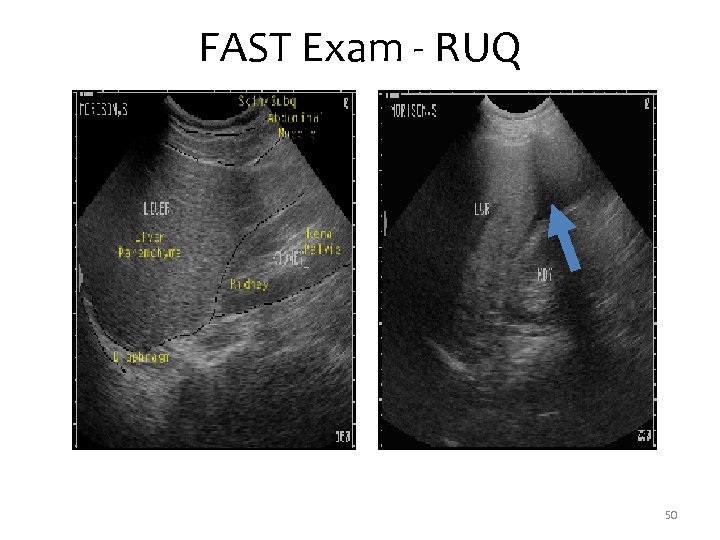

FAST Right Upper Quadrant - Morrison’s Pouch • Between the liver and kidney in RUQ. • First place that fluid collects in supine patient. 49

FAST Exam - RUQ 50